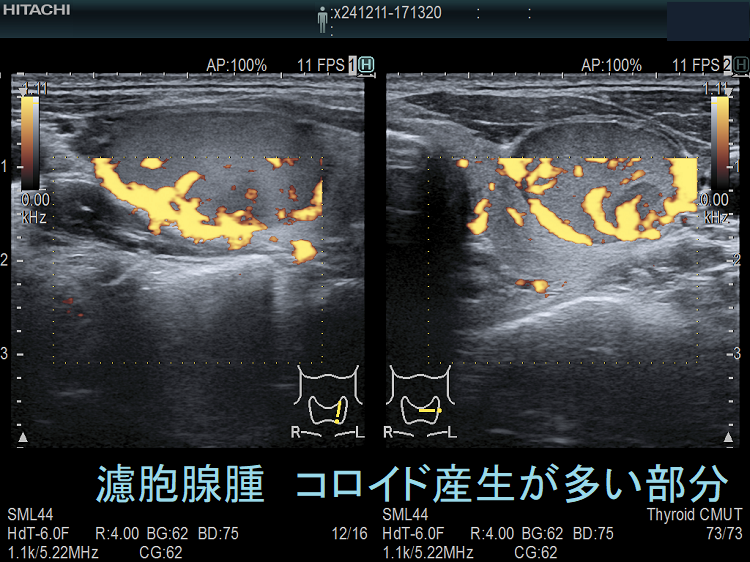

濾胞腺腫内の低エコー領域(コロイド産生が多い部分);濾胞腺腫内にやや低エコーな部分が存在。濾胞癌を疑って穿刺細胞診してみたら、コロイド産生の多い濾胞細胞が採れた。

そもそも、細胞診で良性濾胞腺腫と濾胞癌を鑑別するのは困難につき、例え良性判定でも注意を要します(内部に低エコー領域が存在する濾胞癌)